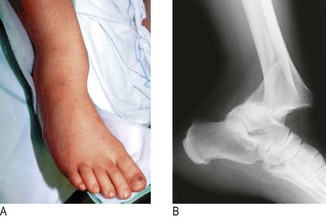

Site: Determine whether the pain originates from a joint (arthralgia) (Box 14.1), muscle (myalgia) or other soft tissue. The site may be well localised and suggest the diagnosis, e.g. the first metatarsophalangeal joint in gout (Fig. 14.2), or in several joints suggesting an inflammatory arthritis.

Fig. 14.2 Acute gout of the first metatarsophalangeal joint. This causes swelling, erythema, and extreme pain and tenderness (podagra).